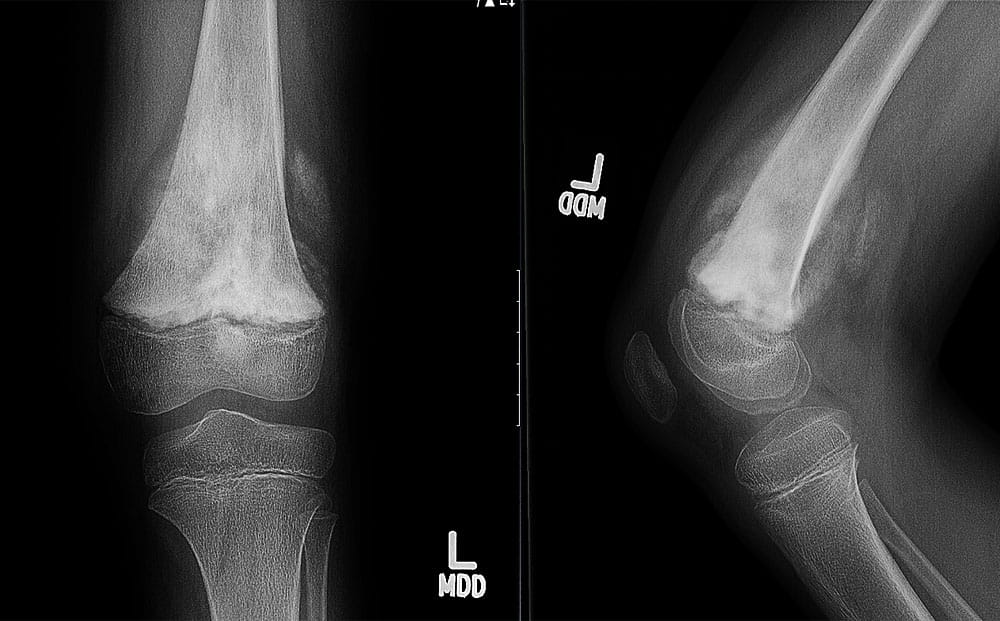

X-ray image of Osteosarcoma

Osteosarcoma: Although primary bone sarcomas are rare, our specialists have the expertise to diagnose and treat all types, including osteosarcoma and Ewing's sarcoma, using a variety of advanced techniques.